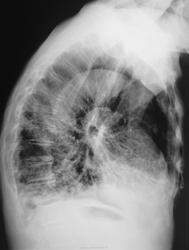

Это конечно шутка, а на самом деле здесь пневмония на фоне порока развития правого легкого. Справа внизу множественные ячейки. Ну и последствия травмы справа. Пневмония, думаю - дело временное.

Типа «сотовое лёгкое»? Нет? интересно, как оно выглядело до болезни?

Неоднозначно всё

Диф Ds поликистоз

бронхоэктазы

пневмосклероз с развитем сотового лёгкого?

Пневмония (возможно грибковая)

Я никак не могу разглядеть просвет среднедолевого бронха, проходим ли он в должной степени? Очень интересно было бы посмотреть контроль